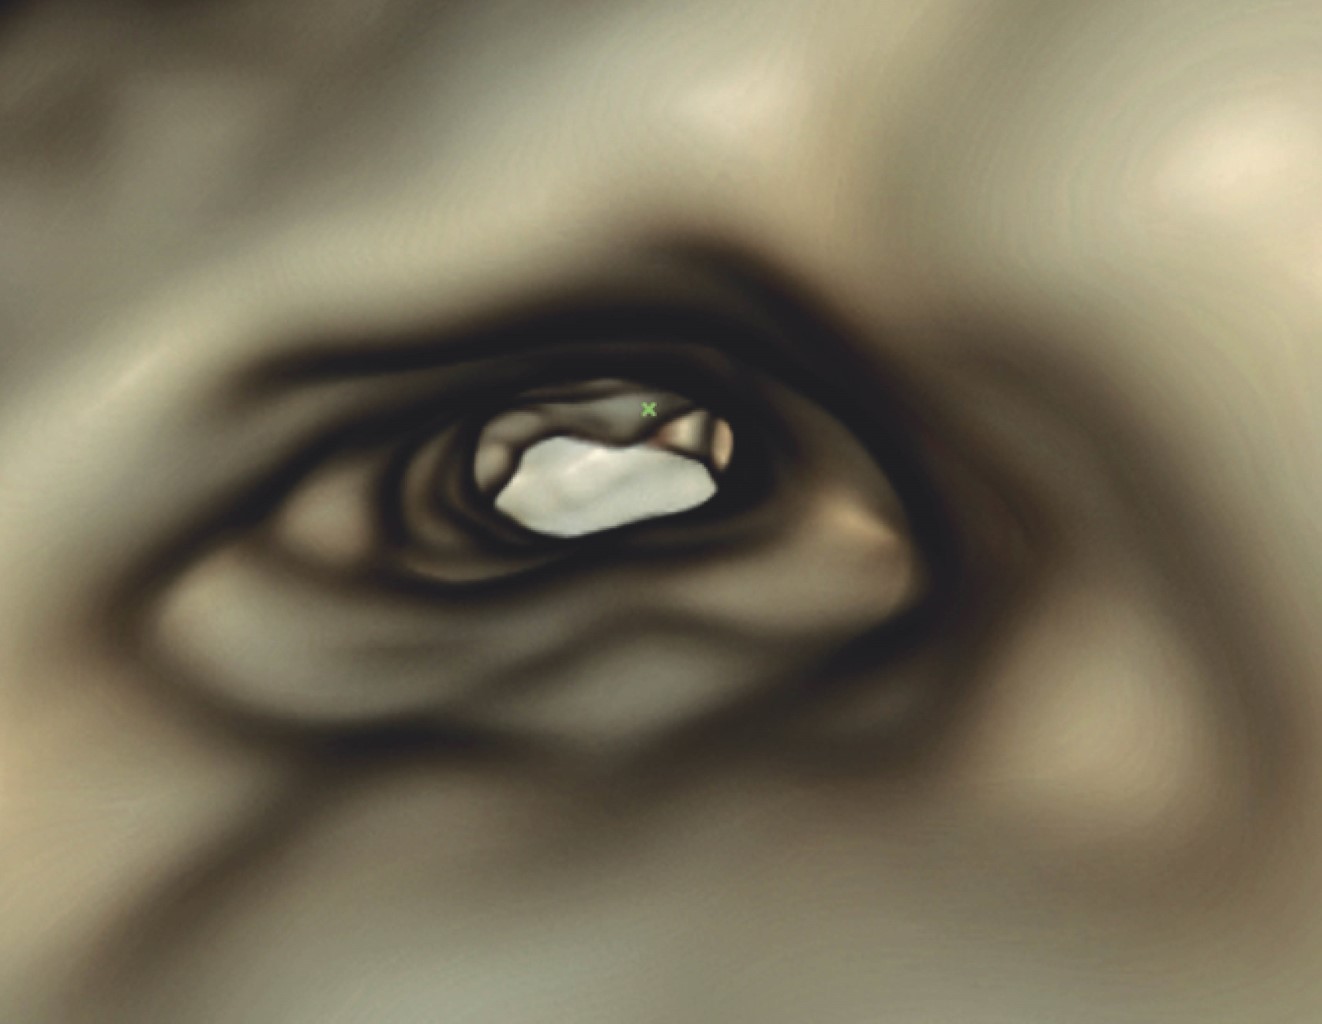

Con la información previa podemos asegurar que el conducto distal se encuentra permeable y tiene un diámetro amplio, características que lo hacen candidato para utilizar en él la herramienta del software OnDemand3D denominada Endoscope, que permite hacer una reconstrucción en 3D del interior del conducto radicular, con esto comprobamos que efectivamente la amplitud del conducto distal es considerable y que debemos tener precauciones al obturarlo, para que el material de relleno no salga hacia el espacio periodontal (Figuras 7, 8 y 9).

Figura 7

Figura 8

Figura 9